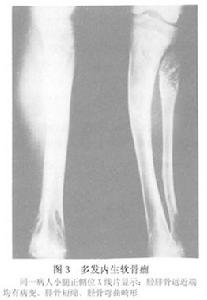

X線檢查:多發內生軟骨瘤病的每一個病變的X線表現與單發內生軟骨瘤相似,但為多發。且有骨骼畸形或短縮。其乾骺端可以增寬。